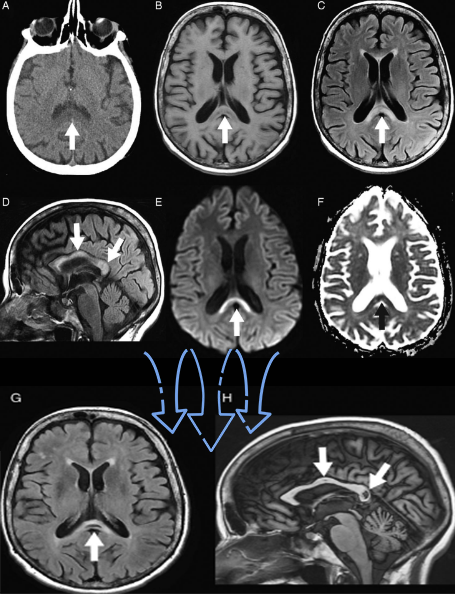

•急性期表现为胼胝体弥漫性肿胀,T1WI呈稍低信号,T2WI及FLAIR呈稍高信号,以矢状位观察最佳,可单独累及胼胝体压部或整个胼胝体,DWI呈高信号,ADC图呈低信号,部分患者可观察到脑室周围白质或内囊受累,少见皮层受累,表现为扩散受限,不强化和强化病例均可见到。如果增强扫描可见胼胝体有不同程度强化,呈小灶状或不规则斑片状,系血脑屏障破坏所致(如本例),本例患者处于急性期。

原发性胼胝体变性急性期:T2WI矢状位(A)清晰观察到弥漫胼胝体病变,FLAIR呈高信号(B),DWI呈高信号(C),ADC图呈低信号。

上排:原发性胼胝体变性急性期

下排:原发性胼胝体变性慢性期,表现为胼胝体萎缩、软化

急性期原发性胼胝体变性(胼胝体压部及体部病变,CT呈低密度,T1WI呈稍低信号,FLAIR呈稍高信号,扩散受限)向慢性期转变,慢性期胼胝体压部病灶出现坏死或囊变,FLAIR呈低信号